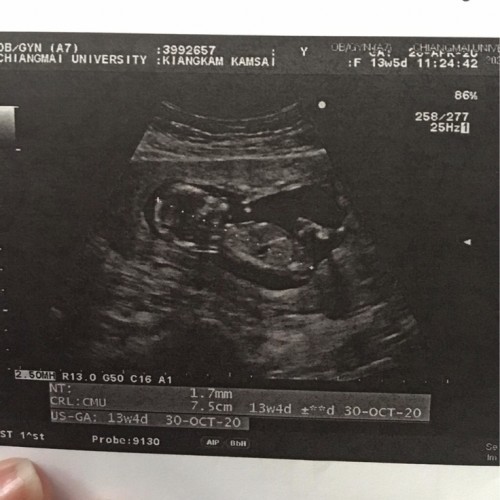

บ้านนี้ตอน13weekค่ะ

ตอน13วีคค้าแม่

ซาวด์ตอน13วีคคะ..